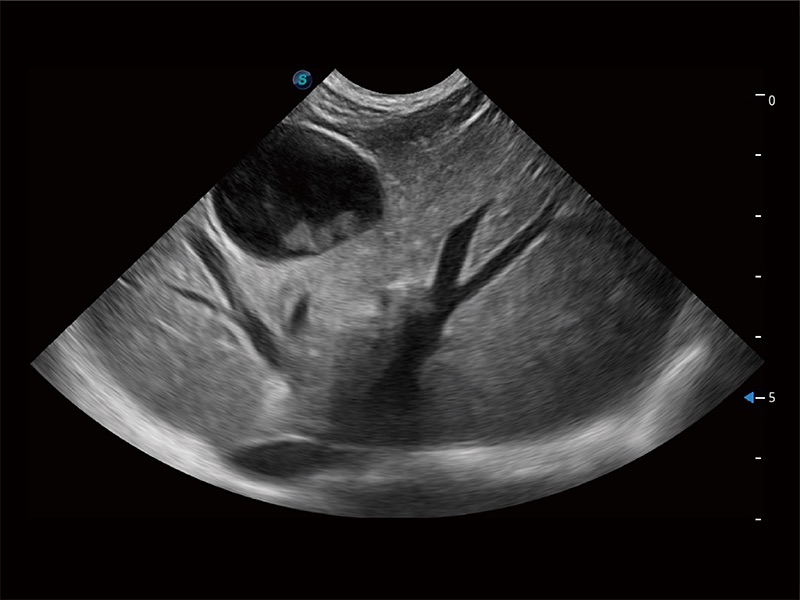

(犬)胎儿主动脉弓立体血流

(犬)胎儿四腔心

优异的基础图像

ProPet 80 全新的动物超声智能软件和丰富的探头群,为动物医生提供了高清晰度和精细分辨率的图像,无论在宠物、马科、畜牧还是实验室动物等应用中都可以轻松应对,为您的日常工作带来满意的体验。